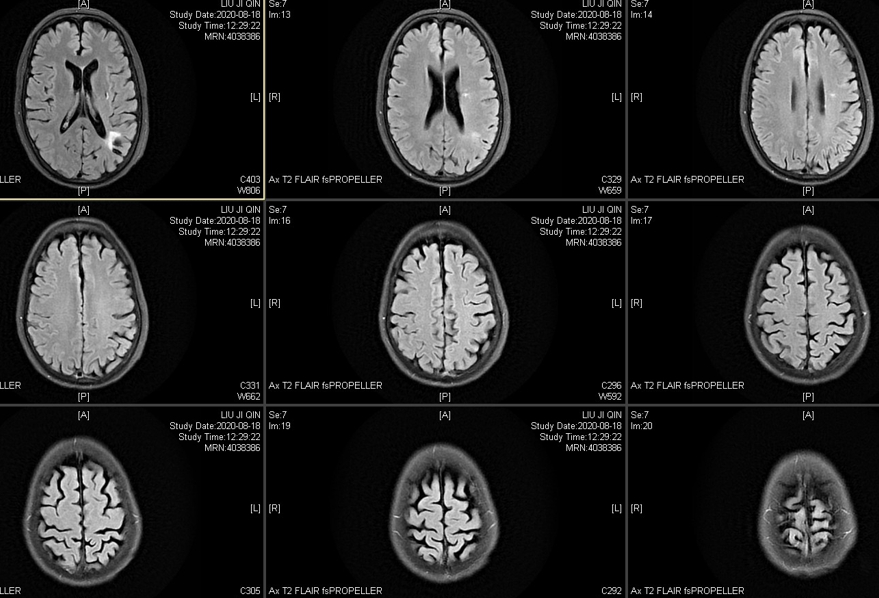

磁共振压水显示左侧多发的脑梗塞:

磁共振灌注也显示左侧大脑半球血供差,但是有一个问题,就是左侧的颞浅动脉额支很细,顶支闭塞了,倒是脑膜中动脉形成了多处向脑内的代偿。